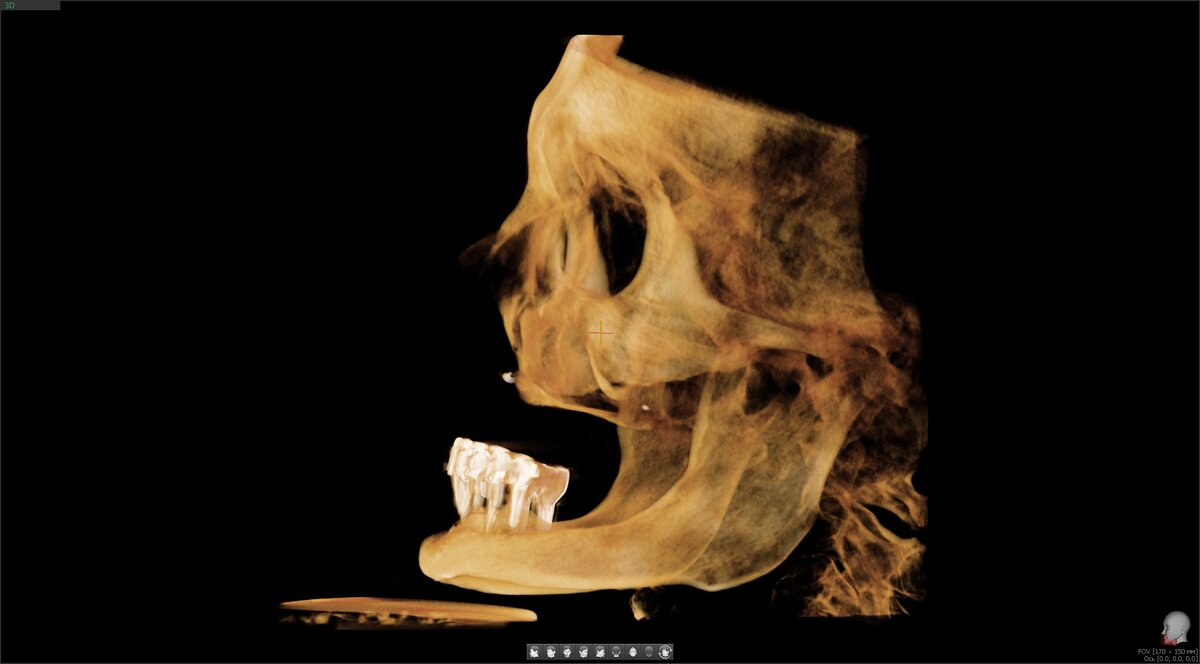

КЛКТ до

Казанков сам не взялся оперировать, наркоза нет, а загвоздка в верхней челюсти - тут без длинных скуловых имплантатов нет шансов обрести уверенно держащийся во рту протез... Отправил в надёжные руки того, кто специализируется на данном виде реабилитации. В "клинику последнего шанса".

Система Nobel, сверхдлинные имплантаты Zygoma. Пациентке были установлены 4 таких имплантата - 2 покороче (около 34 мм), 2 длинных (около 50 мм). Один обычного размера - под нос.

Посмотрим одну сторону (левую, справа точно то же самое) - один длинный имплантат и один покороче: